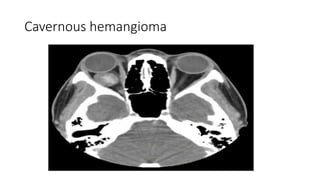

Cavernous hemangioma